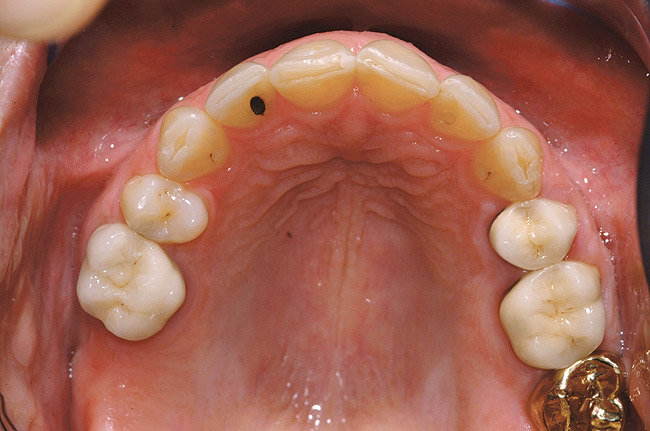

Fig 2 (and Fig 3). Corticotomy SFOT. The patient presented with unesthetic anterior bridgework that was placed at age 14 to compensate for congenitally missing Nos. 7 and 10.

Figure 2

Fig 3 (and Fig 2). Corticotomy SFOT. The patient presented with unesthetic anterior bridgework that was placed at age 14 to compensate for congenitally missing Nos. 7 and 10.

Figure 3